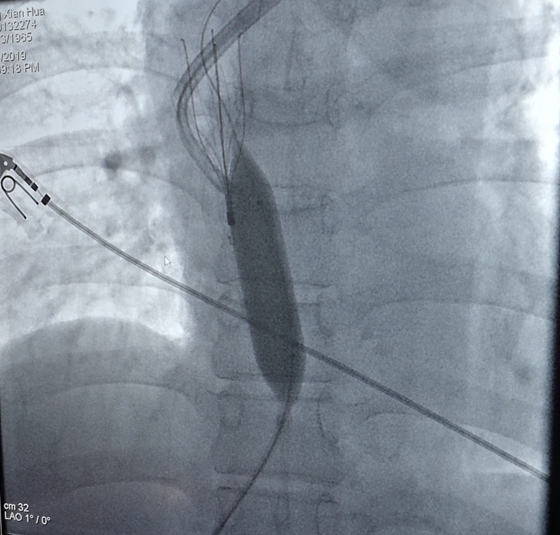

球囊扩张后

住院后给患者行CTV显示:右侧锁骨下静脉,右侧头臂静脉,上腔静脉上部充盈缺损,右侧颈内静脉启始部血栓形成。另外上腔静脉入口至右心房处有静脉狭窄。这就意味着,患者上述多处静脉有血栓,还有上腔静脉狭窄。如果贸然拔出右侧长期管,一旦血栓脱落随血而行,可能导致肺梗死或脑血栓,导致生命危险。成小苗主任、党智杰主治和介入科胡康新主任带领的团队汤金城主治医师,李毅副主任医师,黄彬副主任医师介入团队一同仔细分析了病情。认为可以采取左侧颈静脉置入长期导管,右侧上腔静脉放置静脉滤器防治血栓脱落,拔出右侧颈静脉长期管,球囊扩张狭窄的上腔静脉这种方案,这样既解决了血栓脱落问题,也建立了新的血管通路。2月18日,肾内科和介入科血管通路学组成功为患者置入左侧颈静脉长期管,上腔静脉放置滤器后拔出右侧颈静脉长期管,术后病人颜面浮肿消退。胡康新教授指出,静脉滤器的放置,有效的解决了血栓脱落的问题,是介入科和临床学科合作成功的范例,为病人的治疗提供一个新思路。